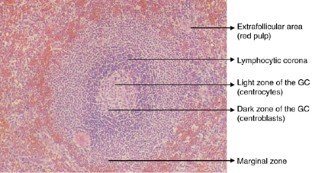

The repertoire of B cells secreting antibodies with unique antigen-binding specificities is produced at two stages: a primary B-cell repertoire is formed in the bone marrow through immunoglobulin gene rearrangements, whereas a secondary B-cell repertoire is generated in the peripheral lymphoid organs (spleen, lymph nodes and mucosa-associated lymphoid tissue) through somatic hypermutation and class-switch recombination upon antigen encounter. The latter events take place within highly specialized histological structures, designated B follicles, which are composed of distinct microanatomical compartments namely the follicle centre, lymphocytic corona and marginal zone. Each compartment comprises a particular subset of B cells, characterized by unique properties, thereby reflecting the complexity and variability in the spectrum of defence mechanisms against invading pathogens. The past years have spawned an avalanche of new data and information that encompasses both the structure and function of each compartment and its B cells. This review incorporates up-to-date information on peripheral B-cell differentiation into a challenging working model, thereby pointing to the structural and functional imprint of both the T-cell-dependent and T-cell-independent immune response on the B follicle. As such, this article aims to form an excellent base for a better understanding of the normal counterpart of B-cell-derived haematological malignancies (leukemias and lymphomas).